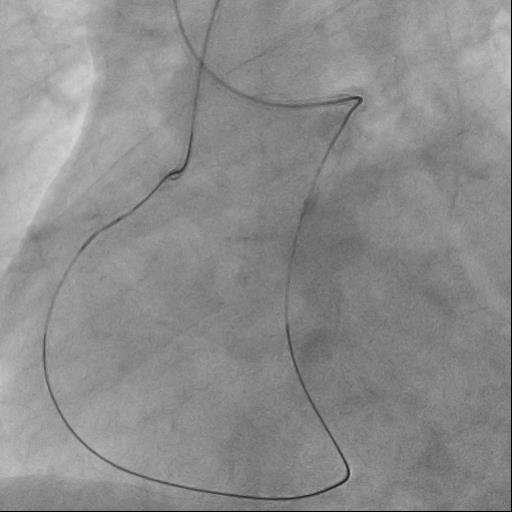

The guide catheter was selectively placed at the RCA orifice, several attempts at antegrade recanalization were performed, after 10 minutes a decision was made to perform retrograde recanalization of the RCA, Sion Blue with the support of a Corsair 150cm microcatheter was successfully introduced through the septal branch into the middle segment of the RCA, escalation to Gaya 2 was performed and recanalization of the RCA was performed. Tip-In was performed in the antegrade guide catheter, the retrograde coronary guide was fixed with a balloon catheter. The retrograde microcatheter was advanced into the proximal segment, however, when performing Corsair, its defragmentation occurred, and the tip of the microcatheter itself was torn off. A decision was made to perform repeated recanalization of the RCA in a new lumen. Recanalization was successfully performed, then Tip-In was performed into the antegrade microcatheter and its successful passage beyond the occluded area. Balloon angioplasty and stenting of the RCA under OCT control with vFR.